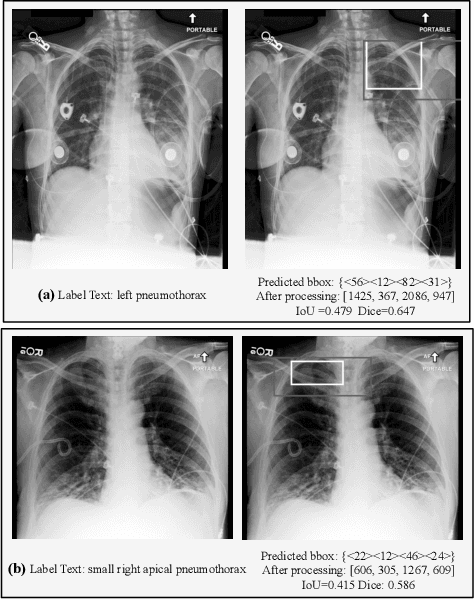

Abstract:Multimodal Large Language Models (MLLMs) inherit the superior text understanding capabilities of LLMs and extend these capabilities to multimodal scenarios. These models achieve excellent results in the general domain of multimodal tasks. However, in the medical domain, the substantial training costs and the requirement for extensive medical data pose challenges to the development of medical MLLMs. Furthermore, due to the free-text form of answers, tasks such as visual grounding that need to produce output in a prescribed form become difficult for MLLMs. So far, there have been no medical MLLMs works in medical visual grounding area. For the medical vision grounding task, which involves identifying locations in medical images based on short text descriptions, we propose Parameter-efficient Fine-tuning medical multimodal large language models for Medcial Visual Grounding (PFMVG). To validate the performance of the model, we evaluate it on a public benchmark dataset for medical visual grounding, where it achieves competitive results, and significantly outperforming GPT-4v. Our code will be open sourced after peer review.